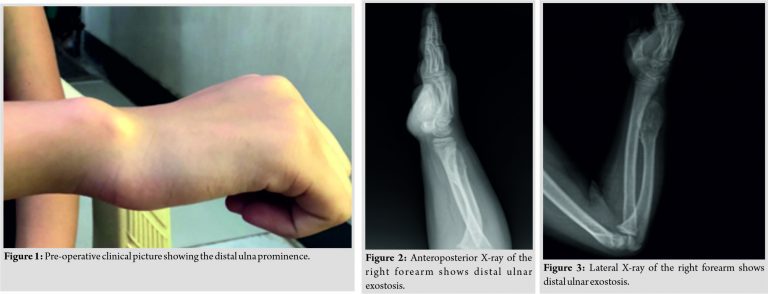

On examination of the right wrist, there was an ulnar deviation of the wrist, which was passively correctable. The distal radioulnar joint (DRUJ) was unstable. There was a palpable, non-tender, osseous prominence in the distal aspect of the ulna (Fig. 1). He had pain on the wrist range of motion and was unable to lift heavy objects. The skin over the affected site was normal with no distal neurovascular deficit. The examination of the ipsilateral elbow and other joints was normal.

Anteroposterior and lateral radiographs of the right forearm show distal ulnar exostosis approximately 5*2 cm in size which was Type I according to Masada classification (Fig. 2, 3). At the wrist, a negative ulnar variance of 15 mm was observed. There was substantial radial bowing compared to the contralateral side and the length of the ulna was 3 cm shorter.